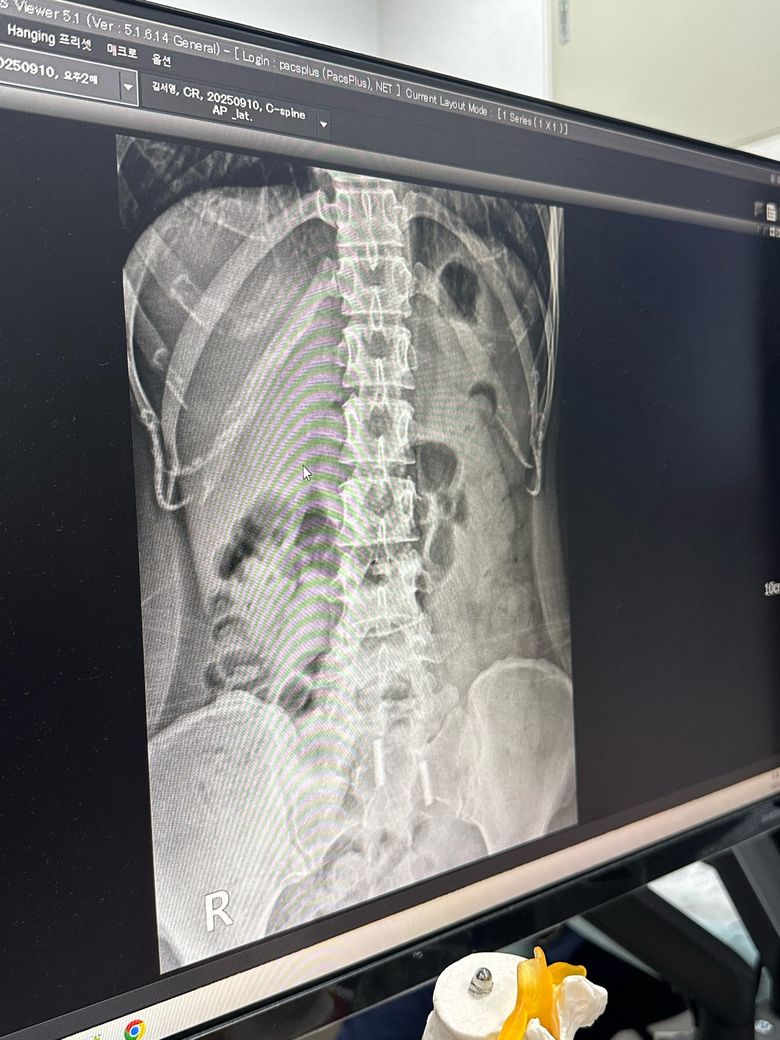

• 2번 째 사진

X-ray상으로 디스크를 정확하게 알 수는 없으며 척추체 사이가 간격이 좁아져 있다면 디스크 이상을 의심해볼 수 있습니다.

X-ray상 골반틀어짐, 척추측만증 등 전체적으로 신체 균형이 틀어져 있는 것으로 보이며 잘 못된 운동은 증상을 더 악화시킬 수 있기때문에 정형외과에서 진료받으시고 체형교정을 위한 도수치료를 받으시는 것이 도움이 되실 것입니다.

다만 디스크 질환의 경우에는 단순히 공간이 좁아진 것 뿐만 아니라 이로 인해 발생하는 신경압박으로 인해 나타나는 증상이 동반되기 때문에, 단순히 공간이 줄어든 것이 디스크가 있다고 보기는 어렵습니다.

마지막으로 엑스레이상으론 현재 디스크를 판단하기 어렵지만 소견 중 디스크 공간이 줄었다는것은 디스크의 가능성이 높으니 주의하시는게 좋습니다.